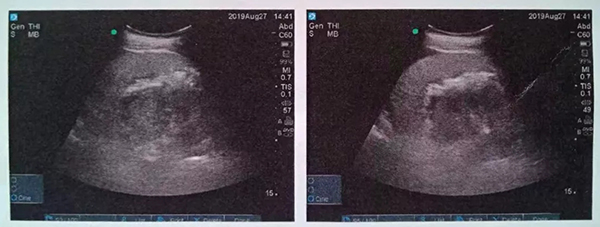

術(shù)中,泌尿外科郭駿博士精心設(shè)計手術(shù)通道,只在患者體表鉆出兩個0.5厘米的小洞,由于患者右側(cè)上位腎位置高,靠近肝臟和肺下葉,容易出現(xiàn)肝臟和肺的損傷,在B超的引導(dǎo)下精確穿刺腎結(jié)石的最高點,逐級擴(kuò)張后建立皮腎通道。這時屢次“惹禍”的腎結(jié)石清楚的顯露在手術(shù)屏幕上,結(jié)石呈淺黃色,表面覆蓋淺褐色的膿苔,然后使用鈥激光將結(jié)石擊碎后取出。歷時一個半小時,結(jié)石全部清除,手術(shù)結(jié)束。